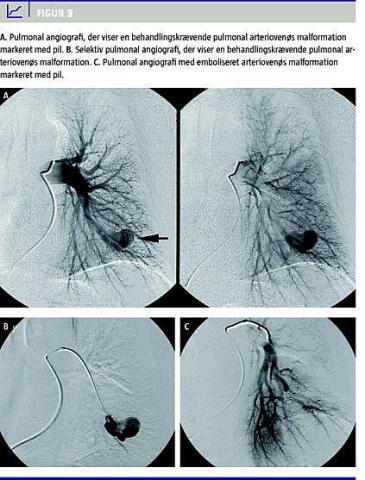

Pulmonale arteriovenøse malformationer

PAVM (Figur 3 ) kan påvises hos 45% af patienterne med HHT1 og hos 12% af patienter med HHT2 [23, 24]. Ubehandlede kan PAVM give paradokse embolier i form af cerebral trombose eller absces i hjernen. En del patienter diagnosticeres primært pga. disse neurol ogiske komplikationer. Ydermere betinger en stor højre til venstre-shunt, at patienten oplever åndenød og cyanose. Endelig kan hæmoptyser forekomme pga. småbristninger i karvæggen eller ruptur af PAVM. Kraftige hæmoptyser med risiko for letal udgang er beskrevet. Det er dog en sjælden komplikation, der i de få tilfælde, den finder sted, hyppigst ses hos gravide HHT-patienter. Endelig er der øget hyppighed af migræne [25-27]. De radiologiske forandringer ved computertomografi og røntgen af thorax fejltolkes i nogle tilfælde som lungecancer, og patienten kan derfor risikere uhensigtsmæssig perkutan biopsitagning. Påviste PAVM bør behandles med embolisering [1, 28]. Radiologisk afdeling på Odense Universitetshospital (OUH) har særlig ekspertise på dette område og varetager behandlingen på landsplan [29]. Ved ubehandlede PAVM bør patienterne i forbindelse med tandbehandling og andre behandlinger, hvor der er risiko for bakteriæmi, behandles profylaktisk med antibiotika for at undgå udvikling af cerebrale abscesser [30].

4. Der påvises PAVM (Figur 3)